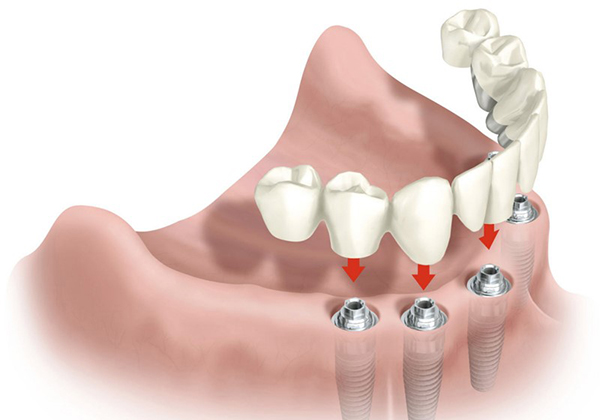

Протезирование зубов в Воронеже Протезирование зубов — один из методов реанимации зубного ряда. Протезирование нужно не только для того, чтобы ваша улыбка вновь стала эстетичной, но и для того, чтобы избежать дефектов дикции или ненужного смещения оставшихся зубов. В стоматологии «32 Плюс» изготавливаются протезы съёмного и несъемного типа из самых качественных материалов, при этом учитываются все физиологические особенности и требования пациента. Мы осуществляются различные способы протезирования верхней и нижней челюсти, полностью или частично восстанавливая зубной ряд. Специалисты с многолетним опытом, лучшие материалы и технологии — залог эффективной работы и качественного результата. Имплантация зубов в Воронеже Имплантация — ещё один метод восстановления зубного ряда, считающийся наиболее эффективным. Имплантат - это титановый сплав, вживляемый в костную ткань и выполняющий роль корня зуба. Внешне похож на металлический штифт. Зубные техники клиники «32 Плюс» обладают уникальными профессиональными навыками и изготавливают имплантаты исключительно из высококачественных материалов. Процедура имплантации зубов обладает многочисленными особенностями и преимуществами, о которых расскажут вам наши специалисты на консультации. Стоматология «32 Плюс» - гарантия безупречной улыбки Кроме стандартных стоматологических услуг в клинике «32 Плюс» проводятся процедуры, направленные на улучшение гигиены полости рта. Мы не используются агрессивные реактивы при отбеливании, поэтому гарантируем белизну и блеск ваших зубов с сохранением их прочности и целостности. Для безупречной стерилизации всех инструментов, приборов и помещений клиники используется система изоляции «Раббердам». Наибольшую эффективность лечения зубов обеспечивает совместная работа стоматологов с ассистентами в «четыре руки». Мы непрерывно работаем над совершенствованием оказываемых нами стоматологических услуг, не только используя различные технологические инновации, но и разрабатывая дополнительные методики лечения. Также наши врачи регулярно обновляют и дополняют свои профессиональные знания: посещают курсы по повышению квалификации, изучают труды зарубежных и отечественных коллег, проходят специальное обучение. Специалисты клиники «32 Плюс» проявляют чуткость и внимательность к каждому пациенту, подбирая каждому оптимально подходящую индивидуальную программу лечения. Стоматологическая клиника «32 Плюс» - с нами Ваша улыбка станет «голливудской»! |